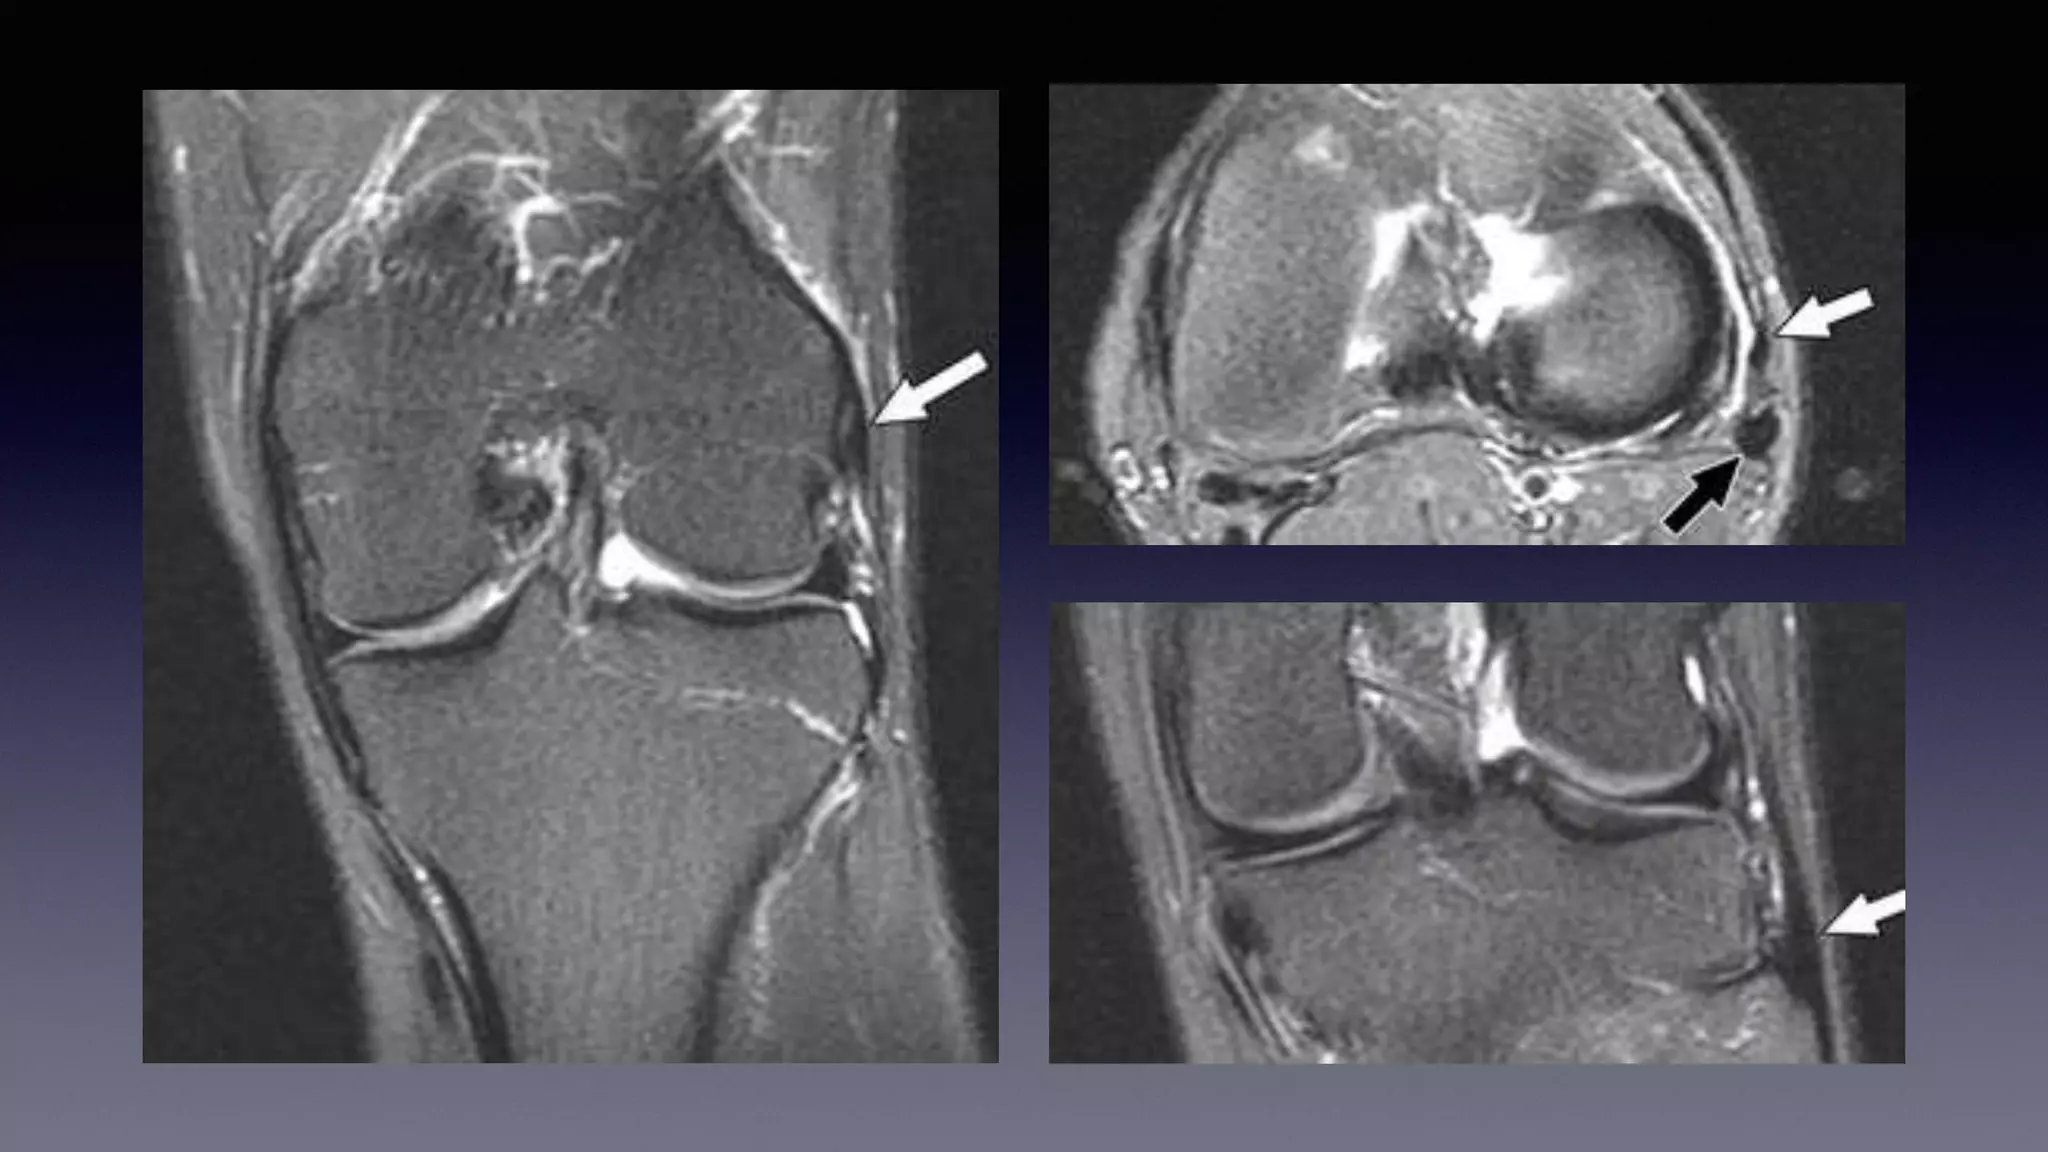

This document discusses using MRI to diagnose ligament injuries in the knee. It begins with an overview of MRI anatomy of the knee and expected pathology. It then discusses specific ligaments like the ACL, PCL, MCL and LCL. For the ACL, it shows images of acute tears, chronic tears and intrasubstance tears. It emphasizes knowing the knee anatomy well and correlating any abnormalities seen with clinical findings in order to apply the appropriate treatment.